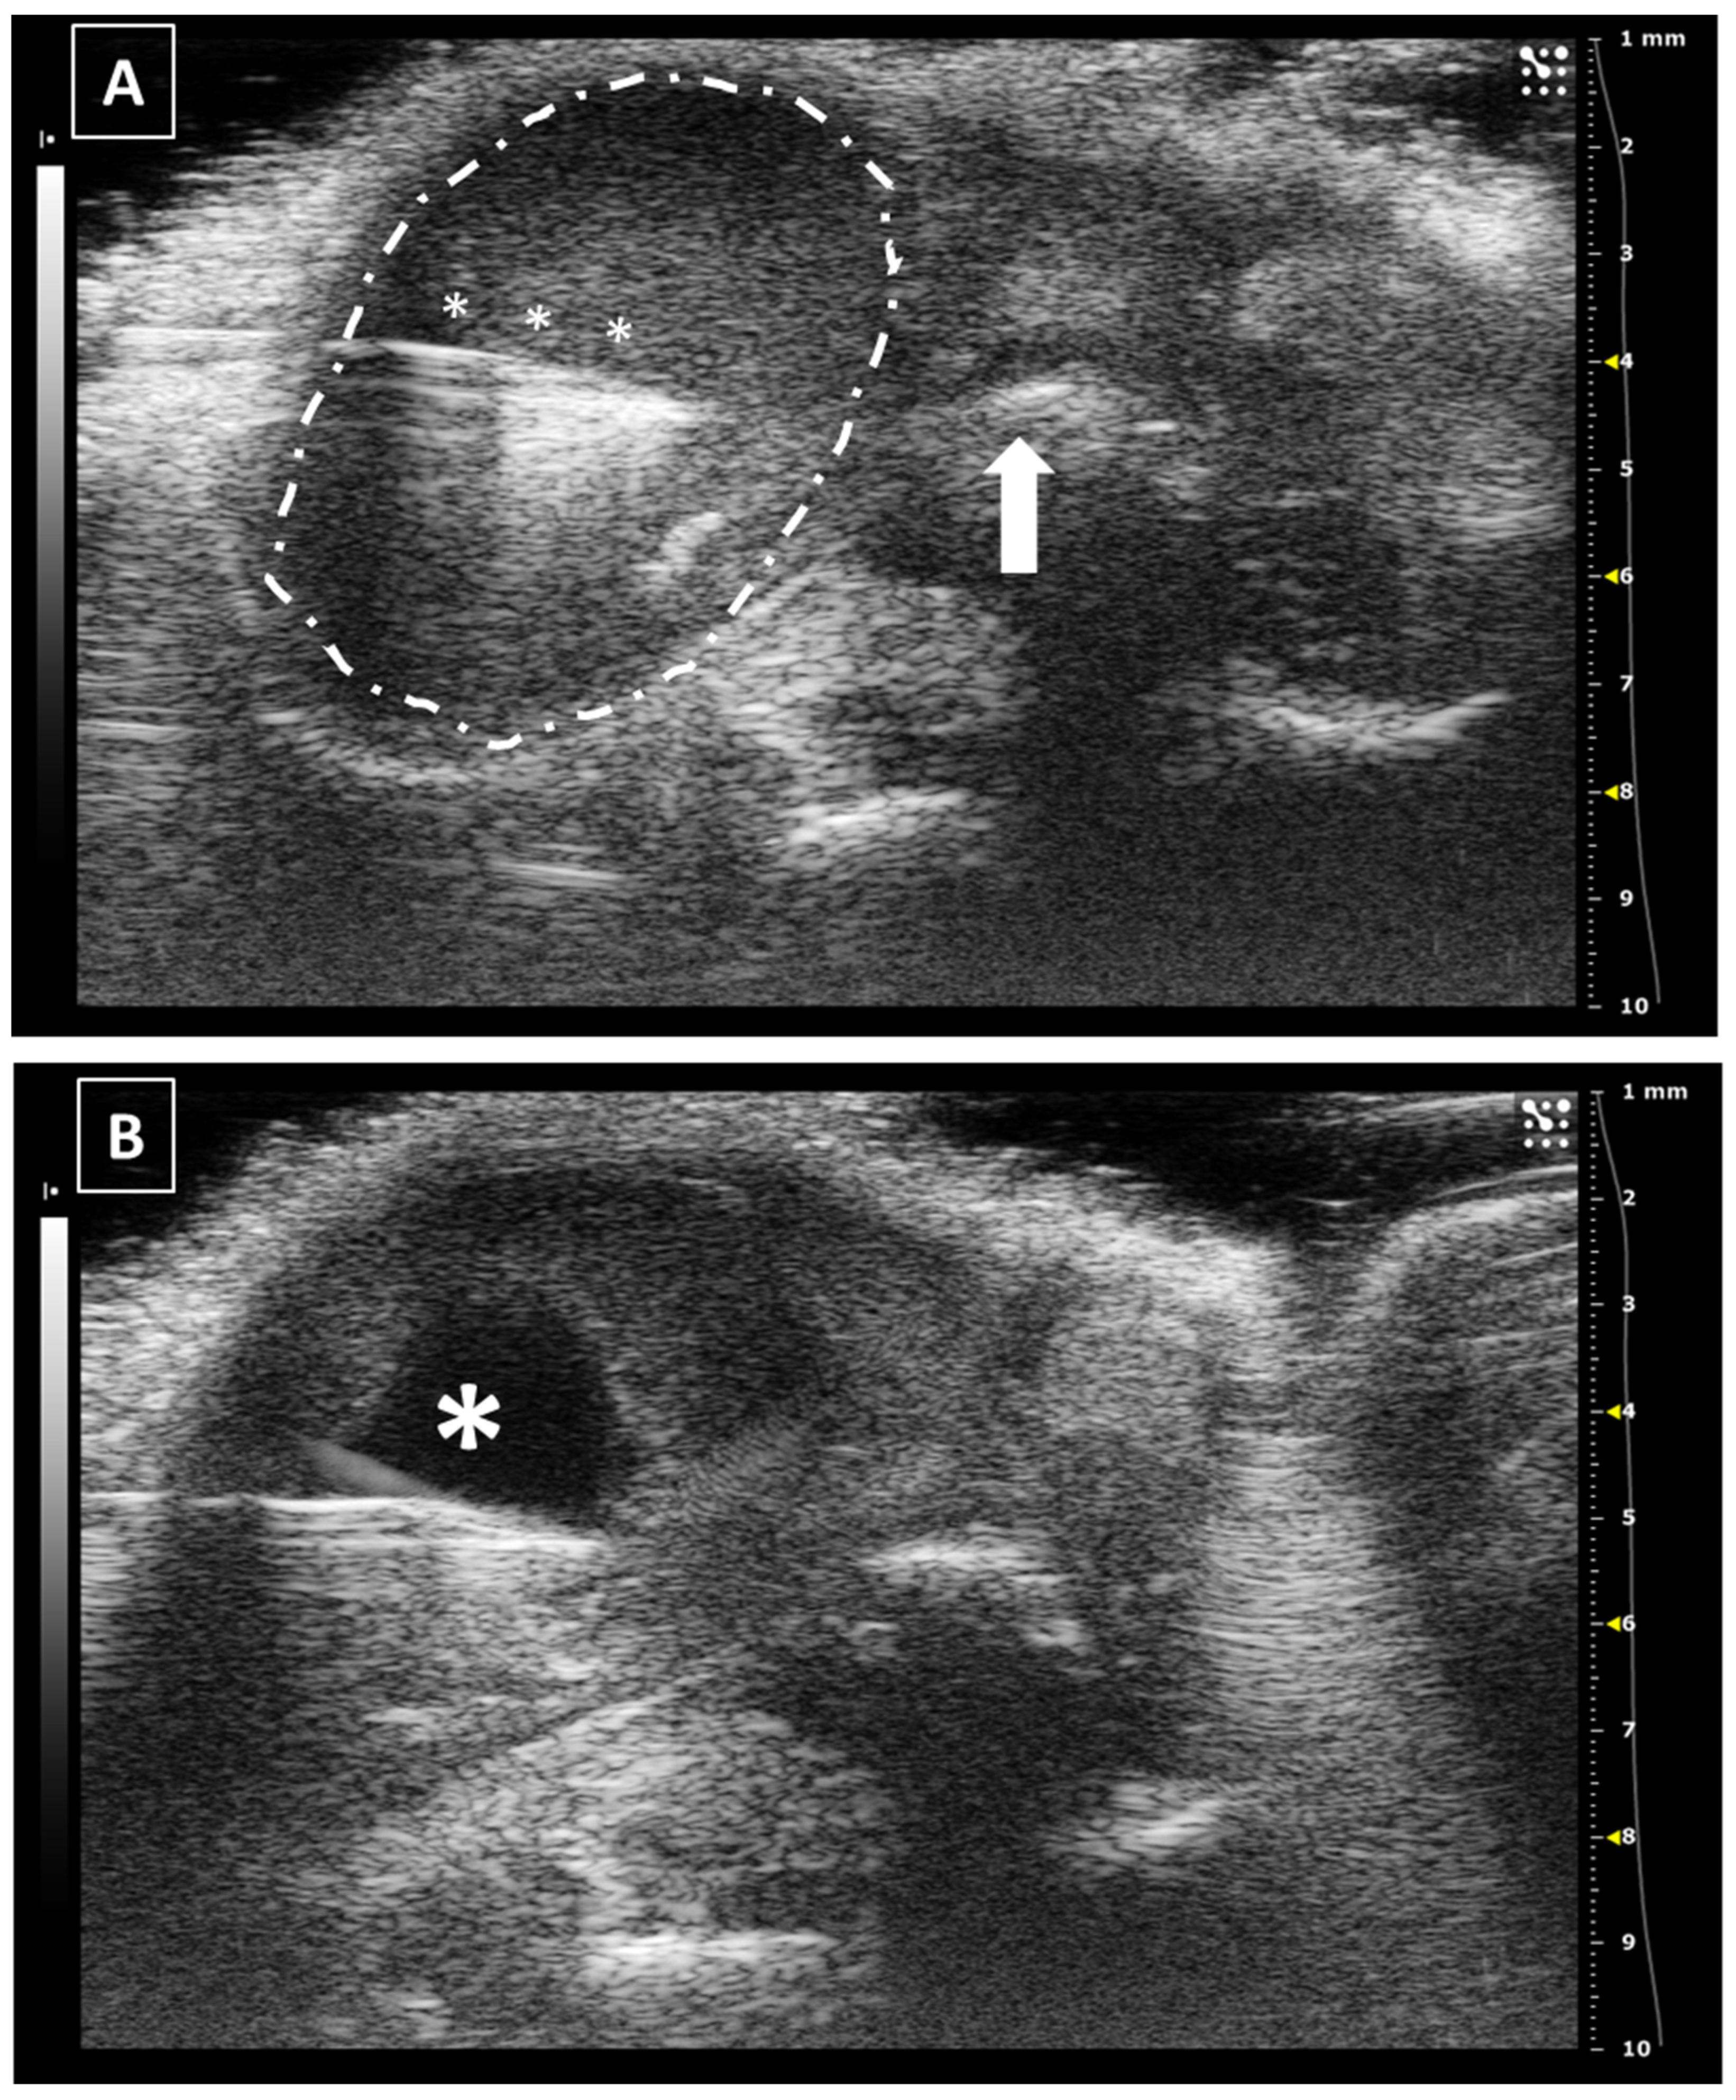

For intrathyroidal injections, a ventral approach is required, positioning the mouse in ventral recumbence and removing the hair of the neck and cranial part of the thorax. The front limbs are fixed with tape in a caudal position, close to the ribs. Intubation of the animal is not required and anesthesia can be supported with a facial mask. After the application of ultrasonographic gel, the scan starts locating the trachea in transversal view at the hyoid bone level. It is recognized due to the acoustic shadow produced by the intratracheal air. Moving the probe caudal, the salivary glands will appear as two superficial, bilateral, hypoechoic, and big structures. At this level, we will need to slightly increase the pressure of the probe against the neck for improving the visualization of deeper structures. Going caudal, a muscular band will appear in the middle line, ventral to the trachea, followed by two bilateral structures, the sternohyoideus and sternothyroideus muscles. The carotid arteries and jugular veins will be visible at this point. The first ones are smaller but have a pulse. We can check the blood flow direction using the Color Doppler mode of the ultrasound system. In a standardized position of the probe (left side of the probe placed over the right side of the animal), the arterial flow should be colored in red and the jugular veins should appear in blue (Figure 2).

The thyroid glands will be located at this level, dorsal and slightly medial to the neck vessels. In a standardized exam, they will appear under the vessels. They are composed of soft tissue, so the echogenicity will be lower than the salivary glands but higher than the vessels. Their shape is irregularly ellipsoidal. The best approach for the puncture is lateral, placing the needle under the ultrasound probe. If the needle is placed correctly in the injection support, we will see it coming from the lateral of the screen (Figure 2). The hardest part of the injection is piercing the skin and for this purpose, we can use forceps for immobilizing the skin. The maximum volume we can inject is low due to the organ size, so more than 10 to 20 microliters in each gland is not recommended [18,19,20].

Figure 2. Thyroid gland injection. (A) Doppler mode of the medium level of the neck, where the jugular veins are colored in blue while the carotid arteries in red. Salivary glands marked with a black asterisks and neck muscles with a white arrow. (B) B mode during the thyroid injection. The needle is marked with white asterisks, and the thyroid gland is surrounded by a dashed line. Trachea cartilage is signaled with white arrows. Images acquired with 40 MHz frequency in B mode and 32 MHz in Doppler mode.